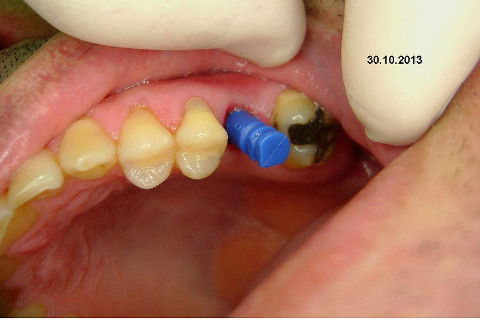

Instalação de um implante em região do 26. Utilizamos um implante cone morse Alvim Neodent 4.3 X 11,5. Foi uma cirurgia muito rápída e minimamente traumática, sem retalho e sutura.

Fotos do caso